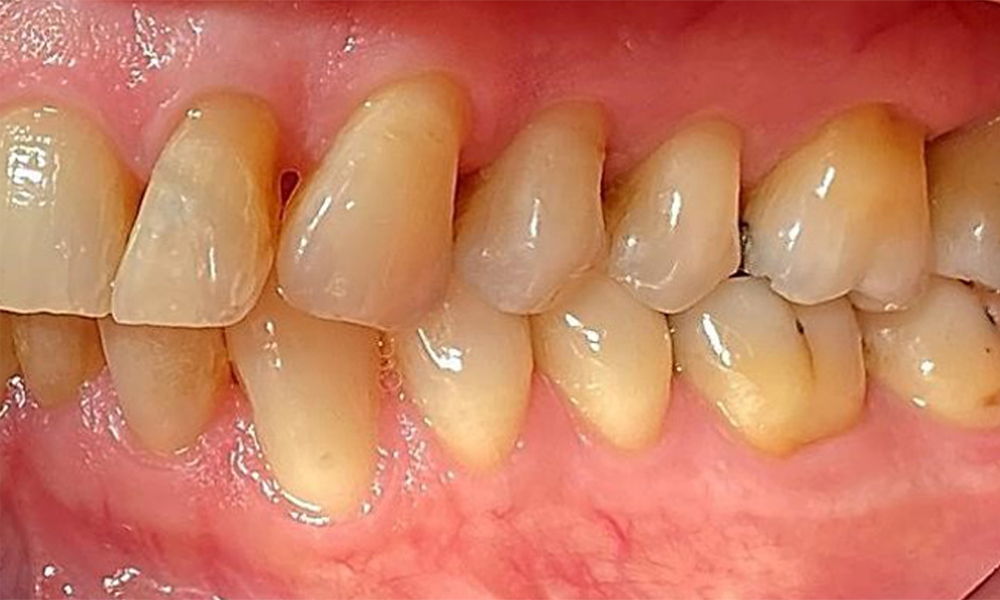

Right lateral view. Loss of the interdental papillae.

Fig. 3 Right lateral view. Loss of the interdental papillae. © Dr R. Krapf

The patient has a full dentition with 28 teeth, which includes amalgam and composite fillings in the molar and premolar regions. There is a visible clinical marginal gap present on tooth 14. Tooth 27 has an adequate gold inlay. There are also generalized attritions and abrasions. (Fig. 2, Fig. 3, Fig. 4, Fig. 5, Fig. 6)

The patient has stage II, grade B periodontitis (5). At 1 to 3 mm, the clinical probing depths were within the physiological range. Localized probing depths of 5 mm were observed on the mesiopalatal aspects on both 17 and 27. There are generalized recessions of 1–3 mm with partial loss of the interdental papillae (Fig. 2, Fig. 3, Fig. 4)